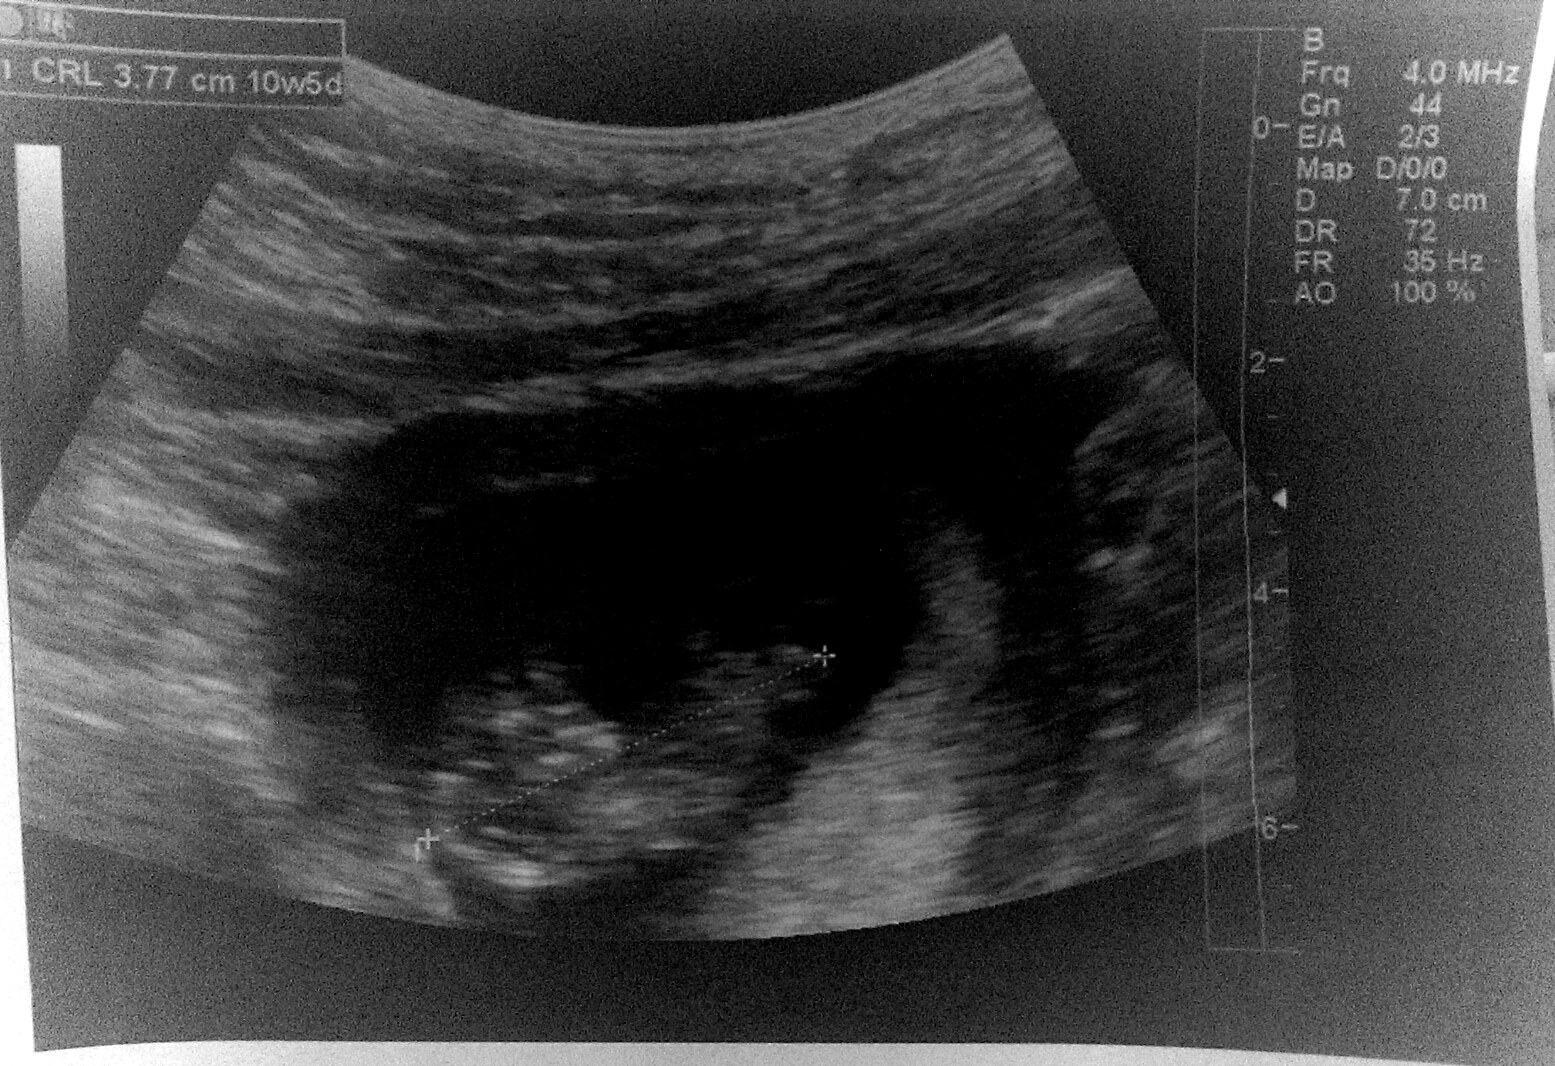

Our 10 week scan that we had this last Tuesday 4/7. Baby measured 10w5d with a heartbeat of 160 bpm. It was a great day for husband and I, not to mention how adorable those little wiggle wiggles were. omgosh, just melted my heart. I am so in love